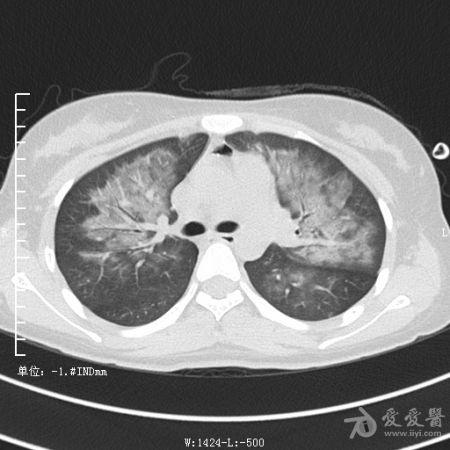

典型支气管扩张及肺水肿CT片

典型支气管扩张肺水肿